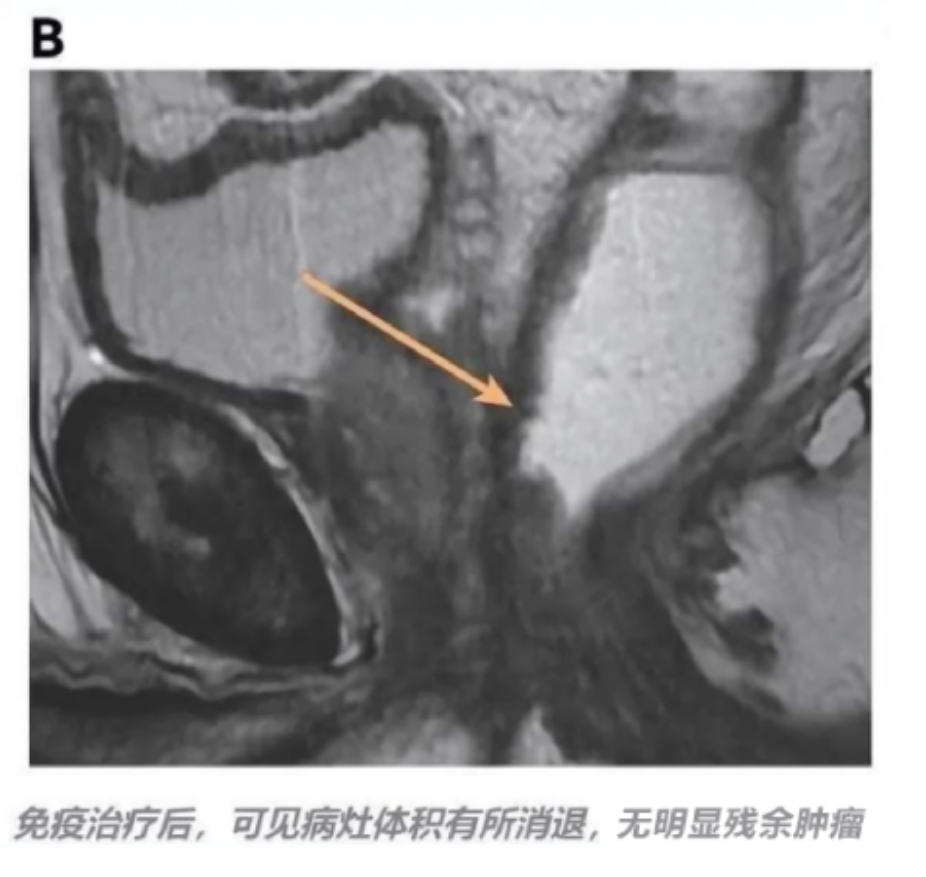

这一结果也让徐先生备受打击,经过家人四处咨询专家后,最终决定使用免疫细胞疗法进行治疗。专家为徐先生定制了 NK 细胞免疫疗法,奇迹发生了。

核磁共振显示原病灶致密纤维化肿瘤消退 2 级,近乎无残留。后续检查虽仍见直肠下部 3.1cm 肿瘤,但对这一部分的组织活检显示,这块区域存在坏死及验证现象,说明人体免疫系统在对抗这一肿瘤组织。

图片